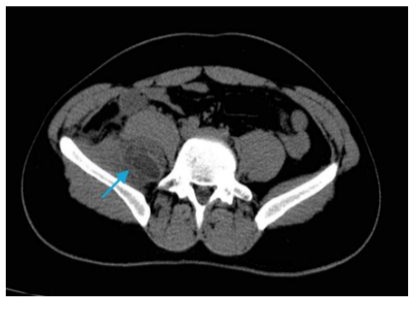

Patient A.G., 26 years old, presented with a one-month history of abdominal pain. A CT scan showed a multiloculated collection centered in the right iliac muscle, measuring 5.0 x 2.5 cm, suggesting an inflammatory process. Surgical intervention was recommended for drainage of an abscess in the iliopsoas muscle. A puncture was performed on the bulging in the right psoas muscle, resulting in immediate drainage of 20 ml of serous secretion. The patient was hospitalized in the ward and showed no significant complaints. He was discharged for outpatient follow-up. Upon return, the patient reported continued abdominal pain, and a new CT scan revealed a multiloculated collection measuring 3.0 x 4.0 x 7.2 cm. The patient was readmitted for further investigation and presented with pain during passive and active movement of the Right Lower Limb (RLL), accompanied by paresthesia for one week. Antibiotic therapy with tazocin and symptomatic treatment were started. No significant clinical improvement was observed, and the collection in the iliopsoas region persisted.

Figure 1: Tomography revealing the presence of a cyst in the iliopsoas muscle region (indicated by the blue arrow).

The patient was referred to the Emergency Department of Hospital Mandaqui due to the presence of fever, lower abdominal pain, pain in the lower limbs, and significant functional impairment. The initial diagnosis indicated chronic hepatitis B, with positive serologies and no documented vaccination history. On December 29, 2023, the patient underwent a Computed Tomography (CT) scan (Figure 1), which revealed a multiloculated collection centered in the right iliac muscle, measuring 5.0 x 2.5 cm, suggestive of an inflammatory process or abscess. On January 5, 2024, a follow-up abdominal CT with contrast showed an increase in the collection, now measuring 6.0 cm in its largest axis. On January 6, 2024, an exploratory laparotomy was performed, with drainage of 20 mL of serous secretion from the right psoas muscle. The procedure included lavage with saline solution, placement of a tube -drain, and initiation of antibiotic therapy with 1g ceftriaxone and 500 mg metronidazole intravenously for 7 days. The culture of the abdominal fluid, collected on January 7, 2024, showed no bacterial growth.